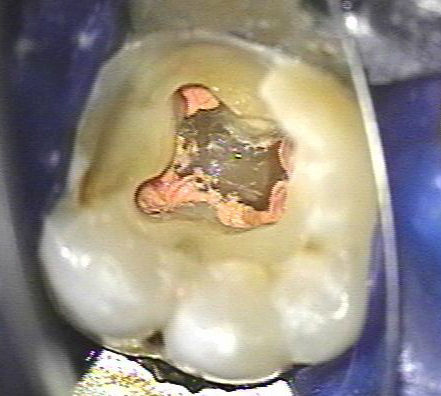

Tratamiento de conductos radiculares

Un tratamiento de conducto es uno de los procedimientos dentales más habituales y necesarios. Este tratamiento puede salvar sus dientes naturales y prevenir la necesidad de implantes dentales o puentes.